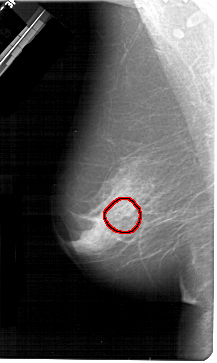

A_1378_1.RIGHT_MLO

FILE: A_1378_1.RIGHT_MLO.OVERLAY

TOTAL_ABNORMALITIES 1

ABNORMALITY 1

LESION_TYPE CALCIFICATION TYPE PLEOMORPHIC DISTRIBUTION SEGMENTAL

ASSESSMENT 4

SUBTLETY 2

PATHOLOGY BENIGN

TOTAL_OUTLINES 1

BOUNDARY